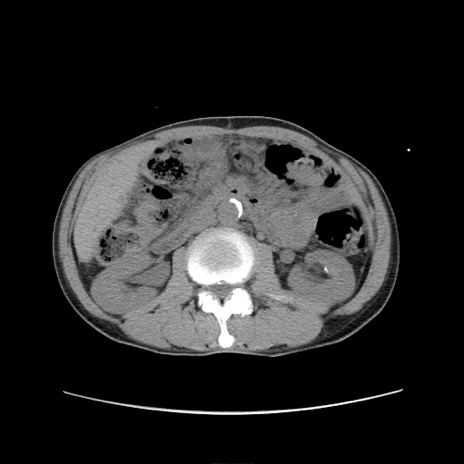

症例11(横断像)

【症例】 60歳代男性

【主訴】 下腹部痛

【現病歴】 本日夜中より下腹部痛の症状認め、受診。

【既往歴】 膀胱癌(膀胱全摘+尿管皮膚瘻術) 、胃癌術後

【身体所見】 BT 35.3℃、PR 58/min、BP 136/98mHg、腹部平坦、軟、腸蠕動音±、ストマ留置あり、左上腹部~正中部に圧痛あり、反跳痛なし。

【データ】WBC 5100、CRP0.01